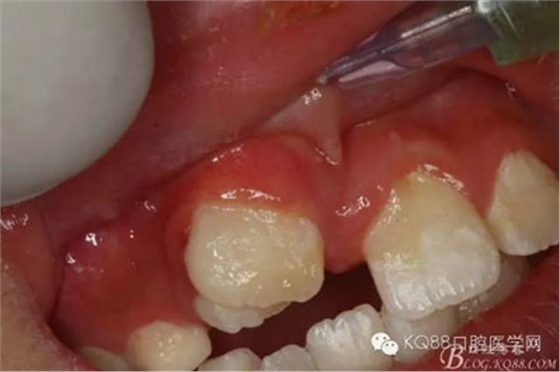

圖1.術(shù)前的患者口內(nèi)照片:11與12完全唇腭向重疊,11與21之間有3mm間隙

圖4.局部粘膜先涂表麻膏

圖5.唇側(cè)無痛浸潤麻醉

圖6.腭側(cè)無痛浸潤麻醉